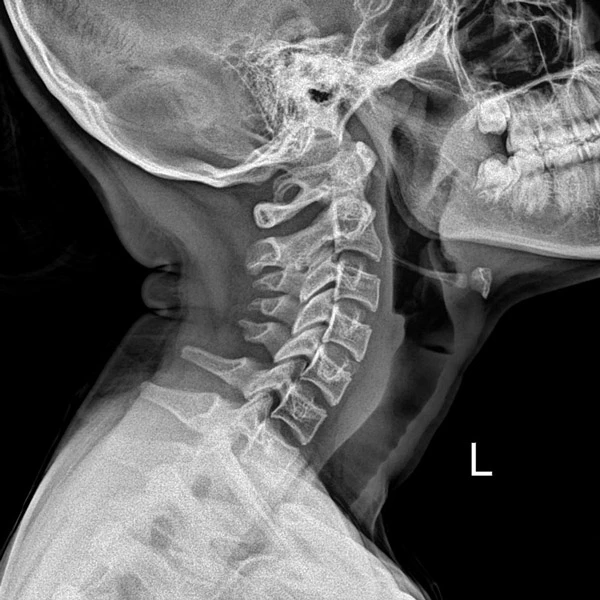

We often begin with a digital posture assessment and X-rays to evaluate the spine’s alignment and function. Based on your results, we’ll create a personalized care plan that may include gentle spinal adjustments, postural training, or traction-based techniques. For patients with structural issues, Dr. Chris may recommend Chiropractic BioPhysics® for long-term spinal remodeling.